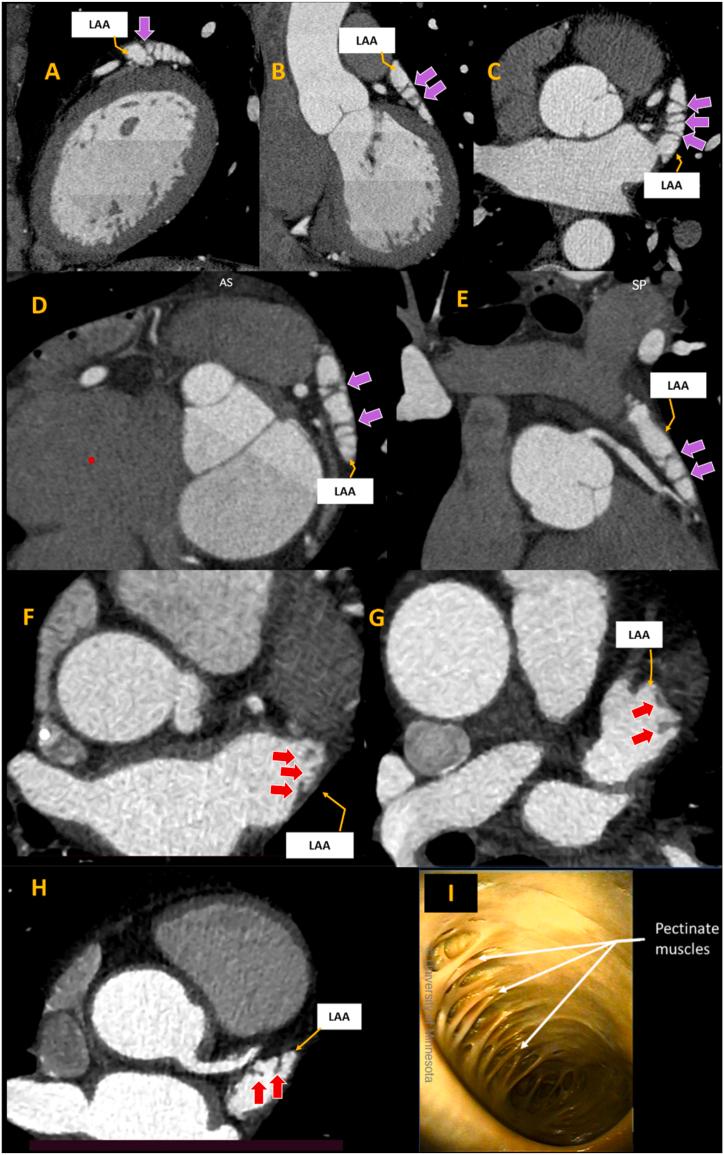

A highly-detailed anatomical study of left atrial auricle as revealed by in-vivo computed tomography.

The left atrial auricle (LAA) is the main source of intracardiac thrombi, which contribute significantly to the total number of stroke cases. It is also considered a major site of origin for atrial fibrillation in patients undergoing ablation procedures. The LAA is known to have a high degree of morphological variability, with shape and structure identified as important contributors to thrombus formation. A detailed understanding of LAA form, dimension, and function is crucial for radiologists, cardiologists, and cardiac surgeons. This review describes the normal anatomy of the LAA as visualized through multiple imaging techniques such as computed tomography (CT), magnetic resonance imaging (MRI), and echocardiography. Special emphasis is devoted to a discussion on how the morphological characteristics of the LAA are closely related to the likelihood of developing LAA thrombi, including insights into LAA embryology.